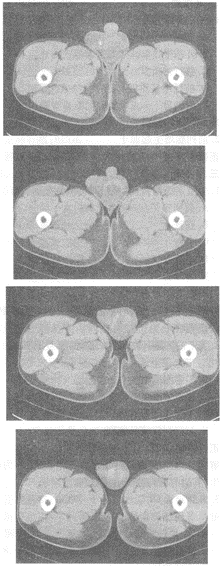

1.男,20岁,外伤1天,左侧阴囊肿痛,结合CT平扫图像,最可能的诊断是

正确答案:A 解题思路:阴囊肿大,左侧睾丸结构不清,可见弧形高密度影,内见低密度区,结合外伤病史,考虑睾丸血肿可能大。